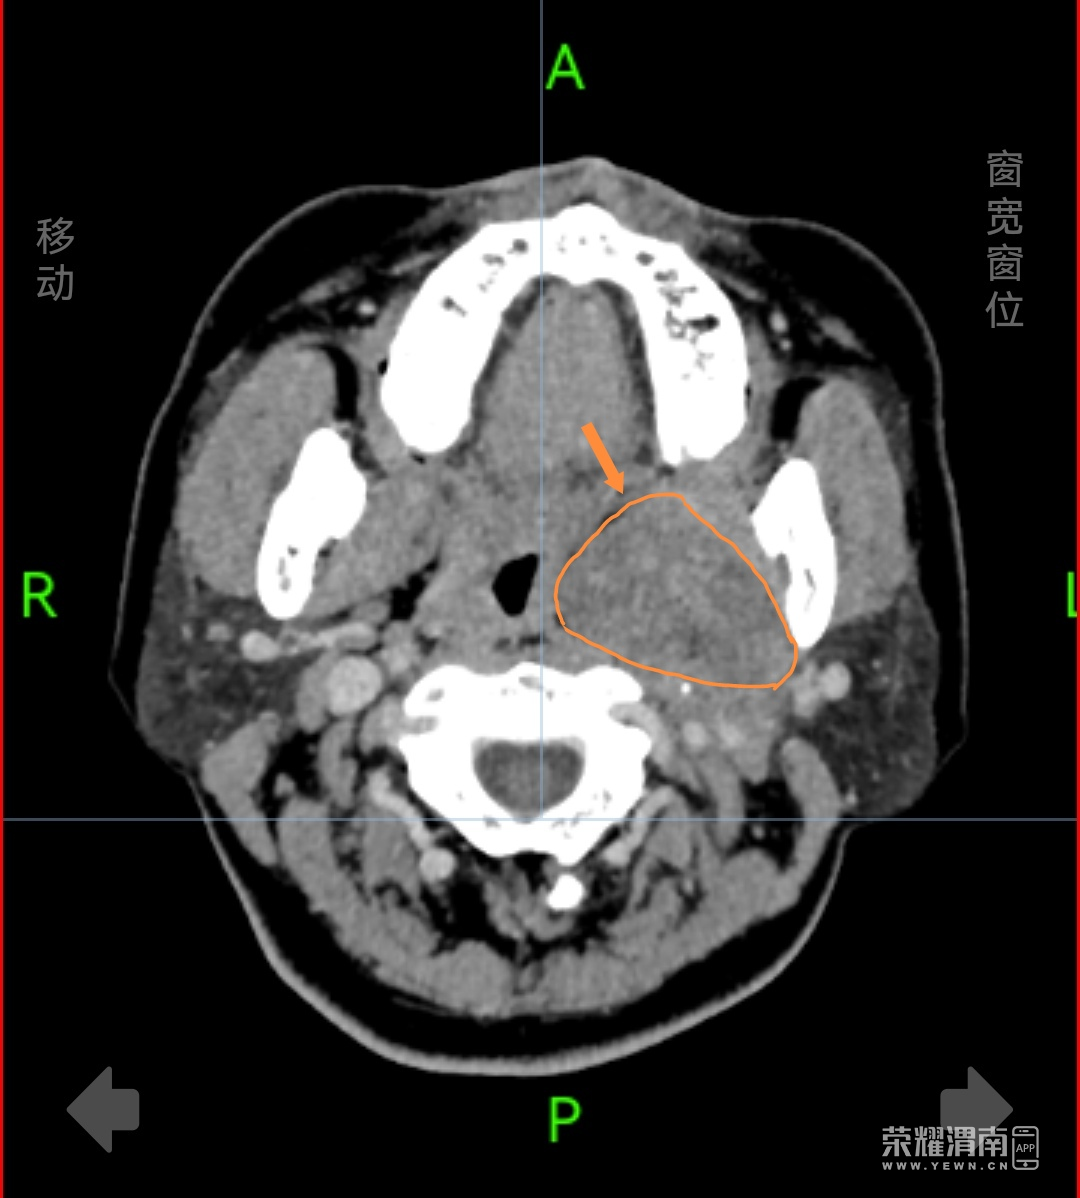

患者杨女士(化名),44岁,在体检颅脑CT检查中发现咽旁间隙存在一处大小约7×6×6厘米的肿物。这个位置特殊——咽旁间隙是位于颈部深处的潜在腔隙,周围毗邻颈内动脉、颈内静脉、颅神经等重要结构,传统手术需要从颈部外部做切口,创伤大、风险高,且术后可能遗留明显疤痕。为寻求更佳治疗方案,杨女士来到渭南市中心医院就诊。

咽旁间隙是位于颈部深处的潜在腔隙,分为茎突前隙和茎突后隙。这个区域发生的肿瘤虽然不多见,但种类繁多,包括唾液腺肿瘤、神经源性肿瘤、血管瘤等。咽旁间隙肿瘤早期症状不明显,可能仅表现为咽部异物感或不适。随着肿瘤增大,可能出现吞咽困难、呼吸不畅等症状。由于位置深在,常规体检难以发现,往往需要CT或MRI检查才能确诊。专家提醒,如果出现持续不缓解的咽部异物感、吞咽困难或颈部无痛性肿块,应及时到耳鼻喉科就诊,进行专业检查。